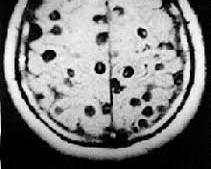

2. Cisticercose:

- Causada por: Taenia solium.

- Transmissão: Ingestão de ovos da tênia do porco, geralmente através de água ou alimentos contaminados com fezes humanas.

- Sintomas: Variam de acordo com a localização dos cisticercos no corpo. Os mais graves ocorrem quando atingem o cérebro, causando convulsões, dores de cabeça e problemas neurológicos.

- Prevenção: Saneamento básico, higiene pessoal, lavar bem as mãos e alimentos.